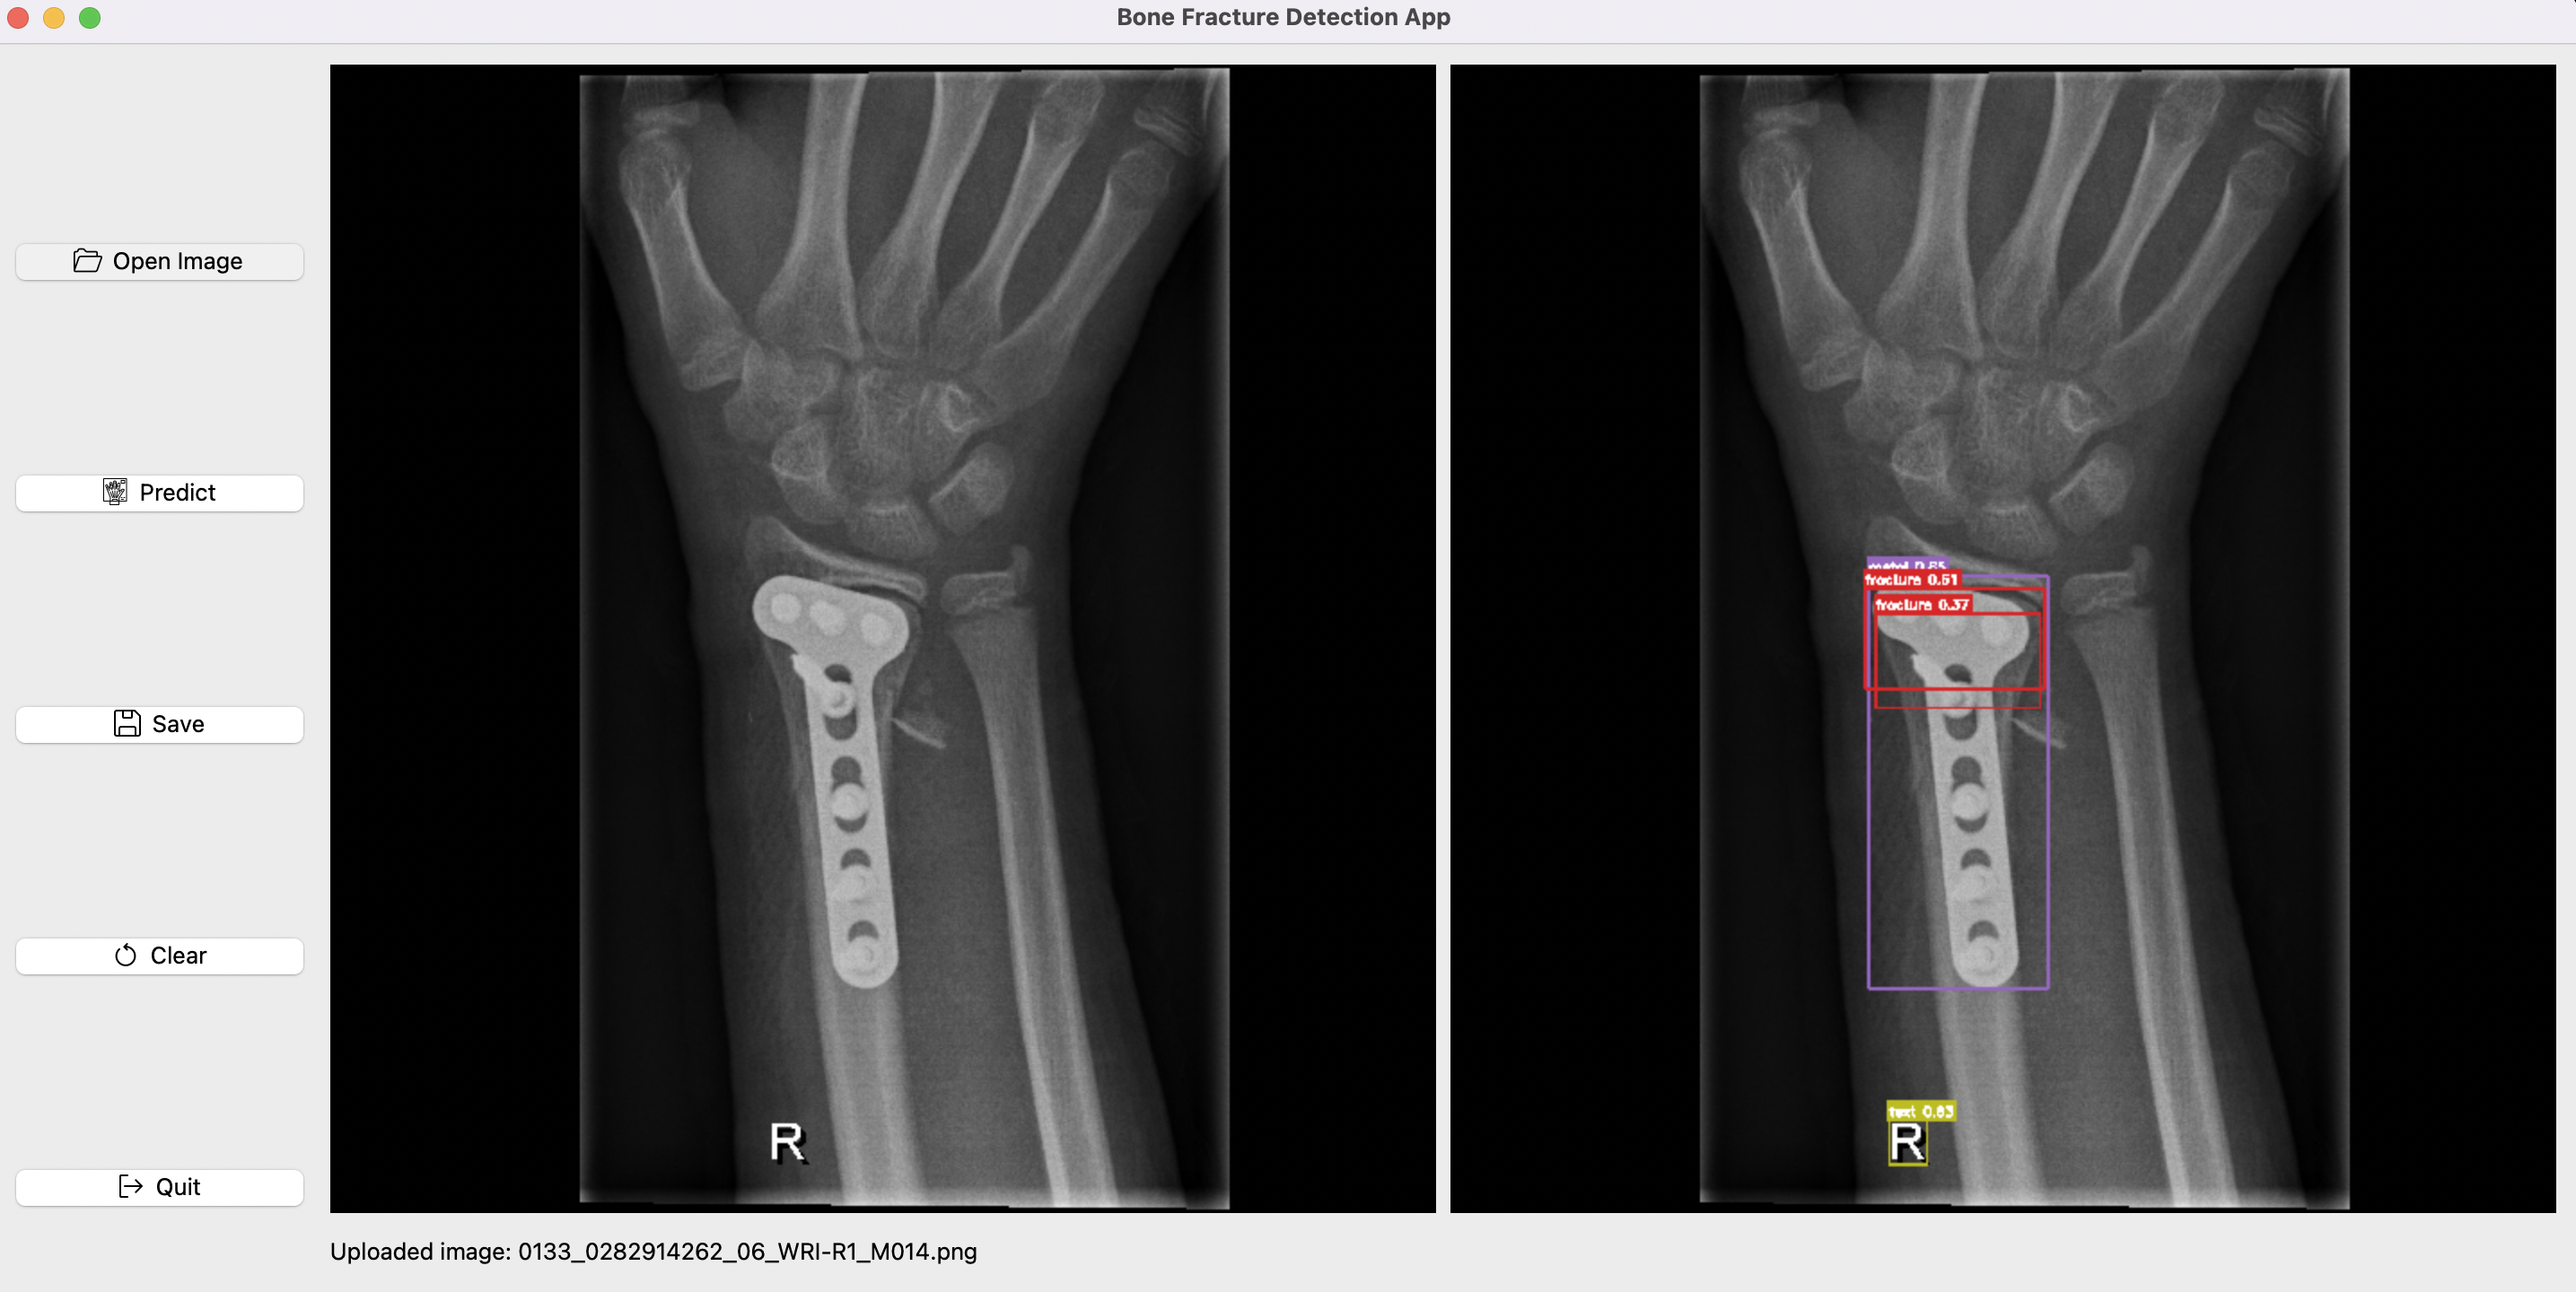

python gui/gui.py

GUI icons were made by Freepik, smashingstocks, photo3idea_studio, Yogi Aprelliyanto, Muhammad Ali, and dmitri13 from www.flaticon.com.

The GUI is done using PySide6, so first install it with:

pip install PySide6

Fig2: Bone Fracture Detection GUI.